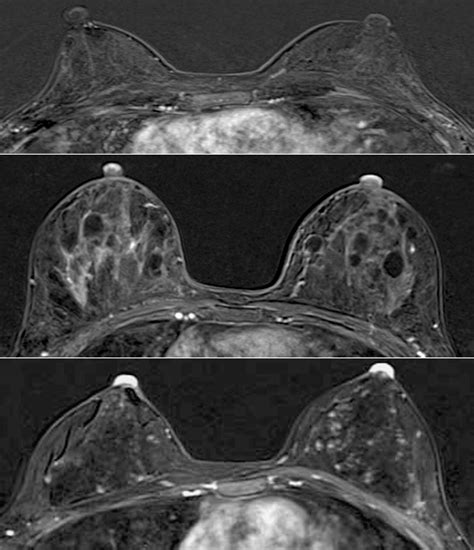

• Imaging Tests: Mammography, ultrasound, and magnetic resonance imaging (MRI) may be used to visualize the breast tissue and detect any underlying tumors. These tests can help determine the extent of the disease and plan the appropriate treatment.

Understanding Paget's Nipple Pictures

Visual aids, such as Paget's nipple pictures, play a crucial role in educating both healthcare providers and patients about the condition. These images can help in recognizing the early signs and symptoms of Paget's disease, facilitating timely diagnosis and treatment. Here are some key points to consider when examining Paget's nipple pictures:

• Appearance: Look for changes in the color, texture, and shape of the nipple and areola. Common signs include redness, scaling, and crusting.

• Symmetry: Compare the affected nipple with the unaffected one to identify any asymmetries or abnormalities.

• Discharge: Note any discharge from the nipple, which may be clear, bloody, or serous.

It is important to remember that Paget's nipple pictures are for educational purposes only and should not be used for self-diagnosis. If you notice any concerning changes in your nipple or areola, consult a healthcare provider for a proper evaluation.